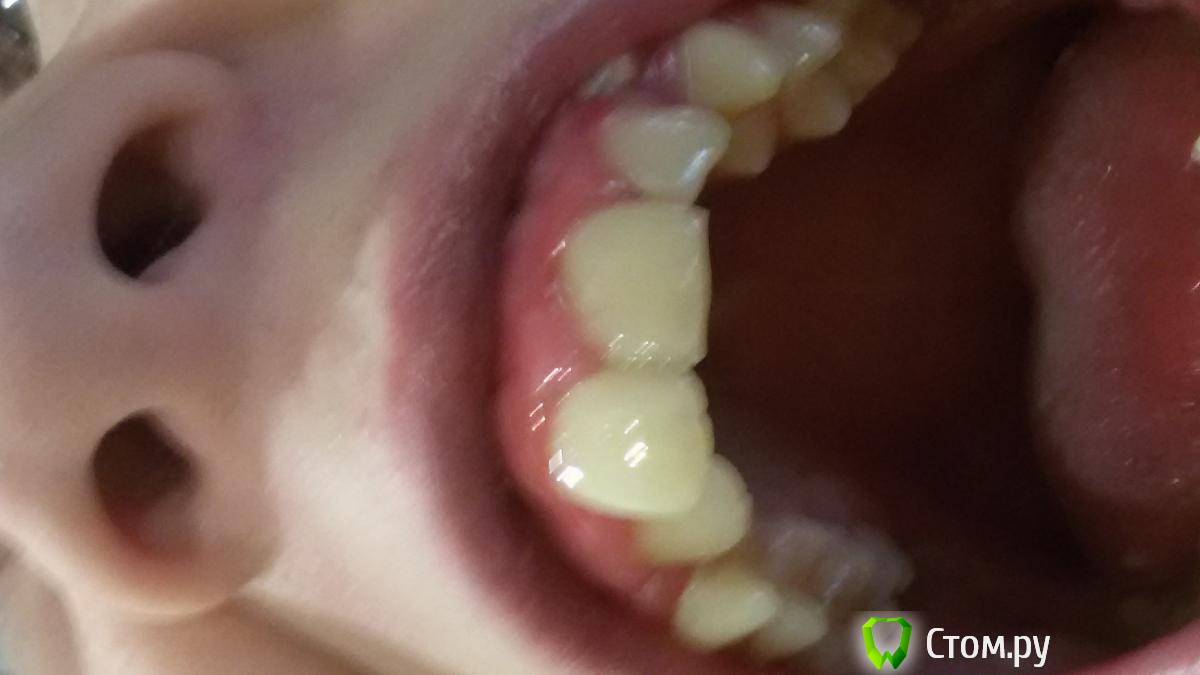

Элько Опубликовано 21 августа, 2014 Поделиться Опубликовано 21 августа, 2014 Здравствуйте! Девочка 12.5 лет . Доктор, сделав панорамный снимок, дала направление на удаление 24 зуба и через два месяца на прием с дальнейшим удалением с другой стороны . Так как клыкам нет места совсем на челюсти они лезут сверху вторым рядом. над 24 уже прорезался а с другой стороны еще нет. Подскажите удаление здоровых коренных зубов как в дальнейшей жизни скажется? И возможны ли другие варианты лечения. Ссылка на комментарий

Ayrat_zub Опубликовано 21 августа, 2014 Поделиться Опубликовано 21 августа, 2014 Здравствуйте! Девочка 12.5 лет . Доктор, сделав панорамный снимок, дала направление на удаление 24 зуба и через два месяца на прием с дальнейшим удалением с другой стороны . Так как клыкам нет места совсем на челюсти они лезут сверху вторым рядом. над 24 уже прорезался а с другой стороны еще нет. Подскажите удаление здоровых коренных зубов как в дальнейшей жизни скажется? И возможны ли другие варианты лечения.упражнение для шеи решили устроить?)) снмики первернутые как попало) можно буз удаения 4-ок, еще одного снимка не хватает Ссылка на комментарий

Ayrat_zub Опубликовано 22 августа, 2014 Поделиться Опубликовано 22 августа, 2014 Я не знаю почему они в разные стороны у меня все ровно было а выгрузилось так .А какой еще нужен снимок? и как без удаления ? Я так понимаю с удалением проще все поставить на место, но как это аукнется в дальнейшем? снимок ТРГ, и кт в области верхних клыков, удалить скорее всего рпидется, но не 4-ки, а зубы мудрости, хотя на верхней челсюти есть варианты) сделайте более четкие фото) по поводу ортодорнта-http://forum.stom.ru/topic/4747-posovetuite-ortodonta-v-gorode-n/ Ссылка на комментарий

Фазлиев Азат Ильдусович Опубликовано 23 августа, 2014 Поделиться Опубликовано 23 августа, 2014 Здравствуйте! Девочка 12.5 лет . Доктор, сделав панорамный снимок, дала направление на удаление 24 зуба и через два месяца на прием с дальнейшим удалением с другой стороны . Так как клыкам нет места совсем на челюсти они лезут сверху вторым рядом. над 24 уже прорезался а с другой стороны еще нет. Подскажите удаление здоровых коренных зубов как в дальнейшей жизни скажется? Лечение однозначно без удаления 4ок! Ссылка на комментарий